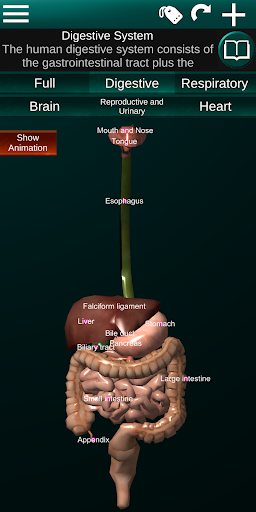

Shows a 3D anatomical model of the main organs of the human body and a description of each one.

* Digestive system, including the stomach, small intestine, large intestine, and an animation of this system.